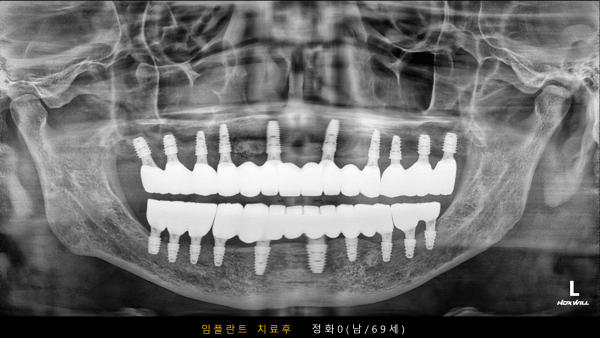

고난도 센터 | 남) 69세